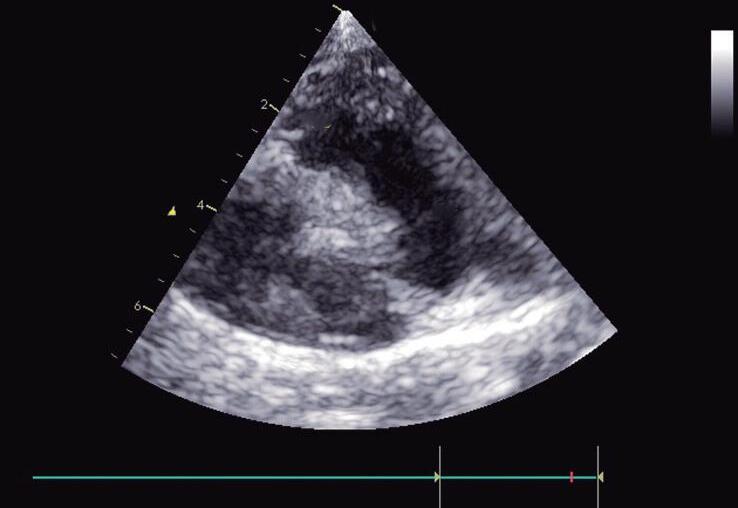

A veia cava inferior (VCI) em longo eixo pode ser visualizada nesse plano. Partindo do plano do eixo curto da VCI e Ao, o transdutor é “rodado” no sentido anti-horário com o index direcionado para o queixo do paciente (posição “12 horas”), inclinado para a direita e ajustado até que o eixo longo da VCI seja visualizado (Fig. 1-3a; ▶ Vídeos 1-3 e 1-4). Isso é muito importante para avaliar o diâmetro da veia cava inferior e sua variabilidade respiratória. O diâmetro da VCI é medido no final da diástole com o modo-M em um plano perpendicular (ver Capítulo 4). Essas medidas podem ser utilizadas para estimar a pressão do átrio direito e, portanto, e o status do volume sistêmico.

Fig. 1-3. Plano de abdômen superior longo eixo. (a) Veia cava inferior (VCI) em eixo longo e drenagem das veias hepáticas. (b) Aorta (Ao) abdominal em eixo longo com tronco celíaco e artéria mesentérica superior originando-se da sua parede anterior. A: anterior; P: posterior; E: lado esquerdo do paciente; D: lado direito do paciente; VH: veias hepáticas; tronco: tronco celíaco; MS: mesentérica.